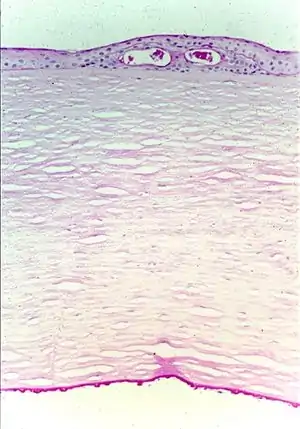

| Fuchs corneal dystrophy. Light microscopic appearance of the cornea showing numerous excrescences (guttae) on the posterior surface of Descemet's membrane and the presence of cysts in the corneal epithelium beneath ectopically placed intraepithelial basement membrane. Periodic acid-Schiff stain. From a review by Klintworth, 2009.[1] | |